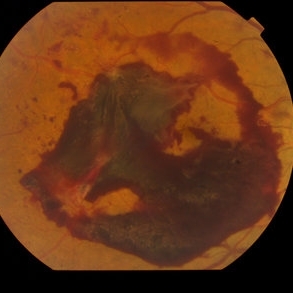

Proliferative Diabetic Retinopathy with Subhyaloid hemorrhage

Oct 18 2012 by Suber S. Huang, MD, MBA, FASRS

43 year old diabetic man with proliferative diabetic retinopahty, subhyaloid hemorrhage, ischemia, neovascuarization.

Photographer: Stacie Hrvatin

Condition/keywords: ischemia, retinal neovascularization, subhyaloid hemorrhage